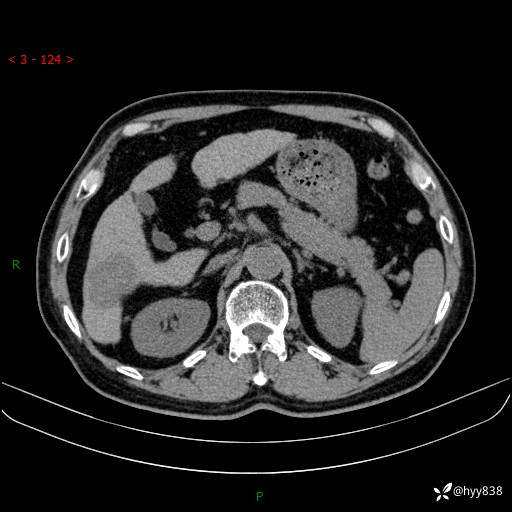

肝脏CT平扫